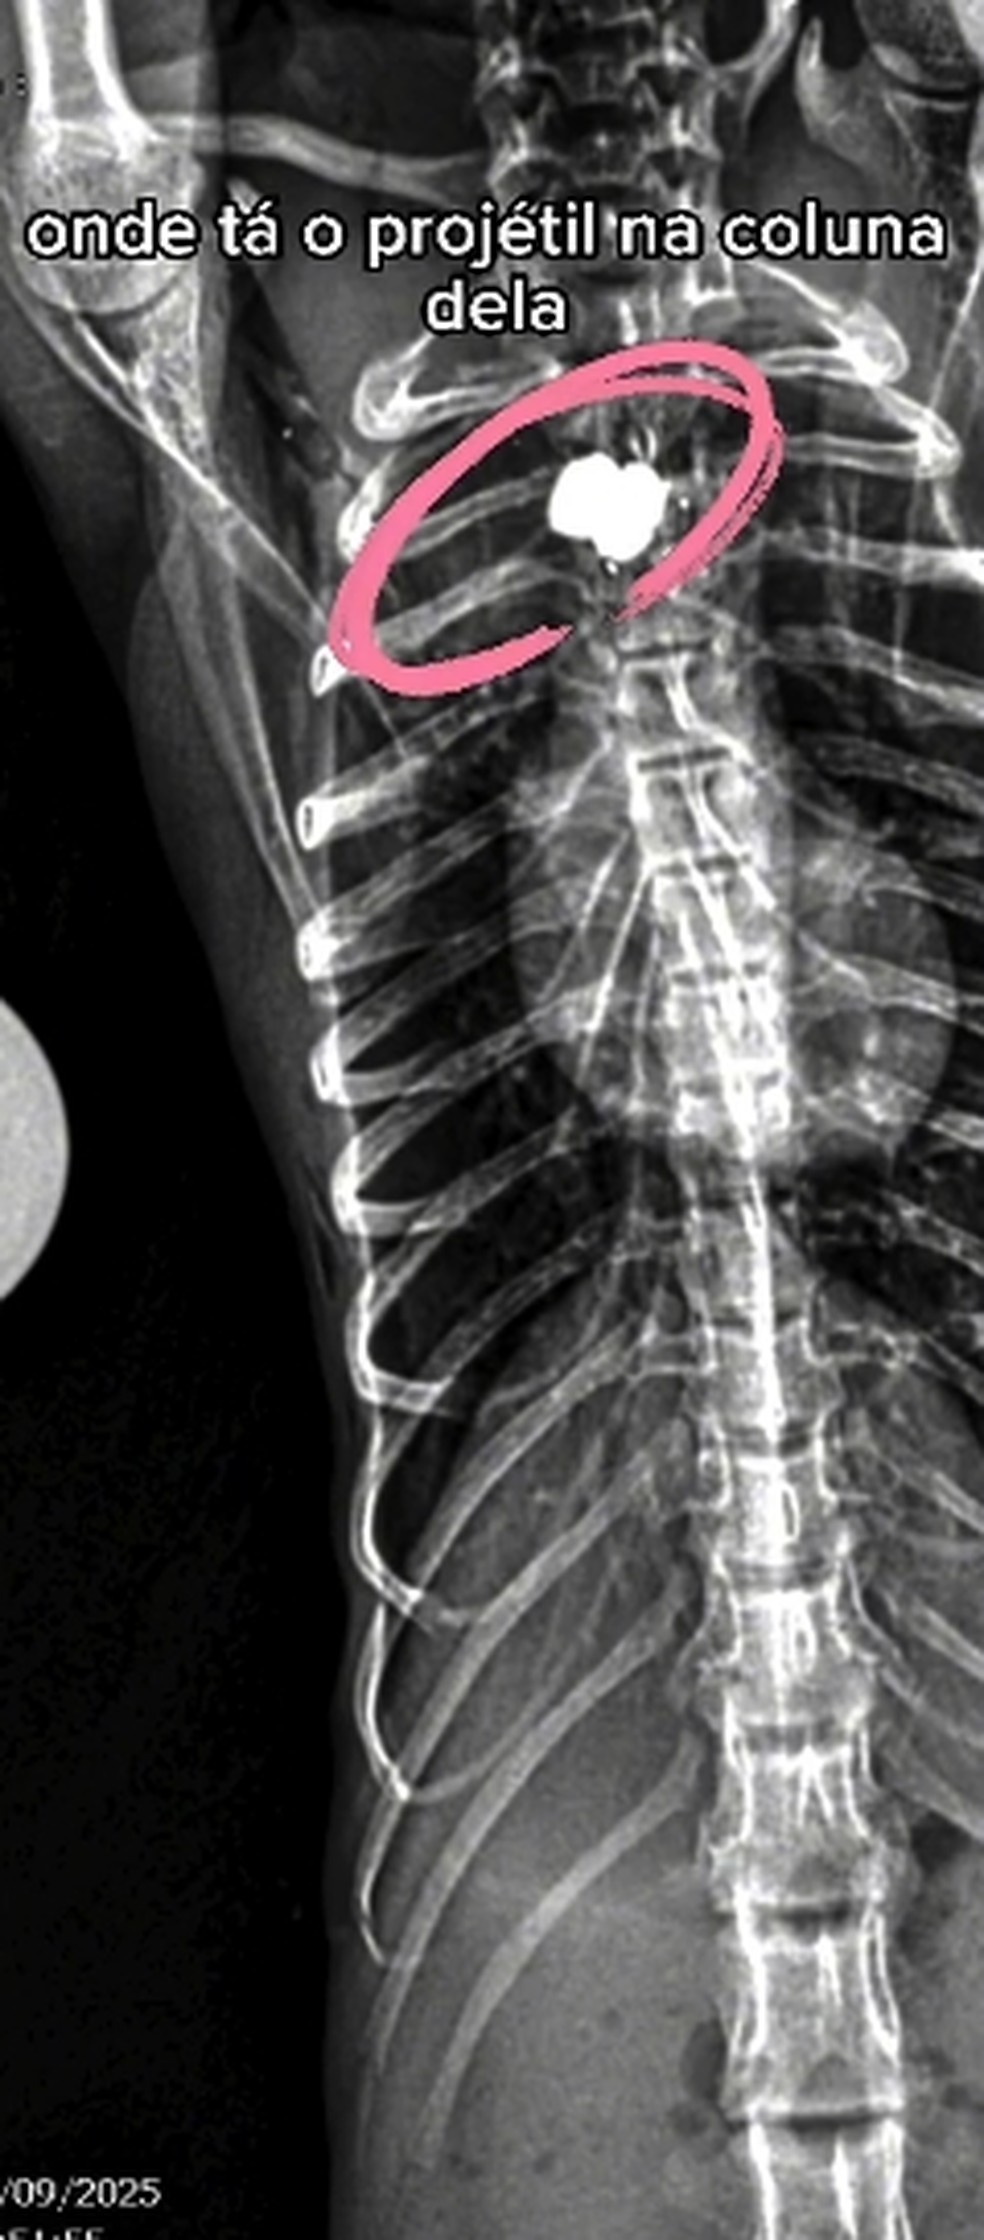

O animal, apelidado de Maria, tinha sido baleado na região cervical por um chumbinho, o que a deixou paraplégica.Segundo o Instituto, Maria recebia cuidados diários, incluindo aquecimento e alimentação assistida.

“Maria era uma fêmea de macaco-prego que não resistiu ao procedimento anestésico, depois de ter sido vít|ma de um tir0, que a deixou paraplégica.”, disse o Institute Vida Livre, em um post no Instagram.